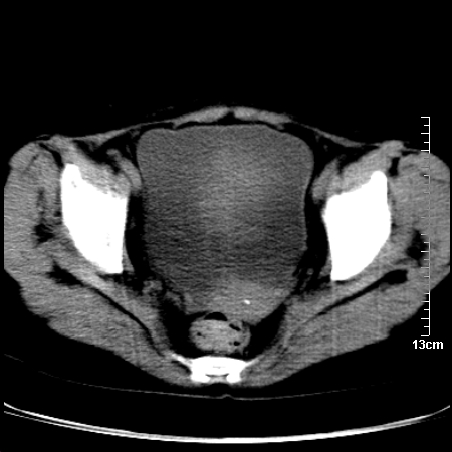

术前的疏忽,手术前诊断阑尾炎,但是没有常规做b超,导致术后1周检查发现 1。实性包块?2。腹腔术后脓肿?

病史:病人一周前诊断阑尾炎,未做b超,手术发现阑尾化脓,(没有留意有无包块),术后1周病人发热,血象:1.6万,做b超发现,随ct检查,上传图片

巨大囊实性包块,边界大部尚清楚,不太像脓肿的表现。应该做个增强检查除外盆腔肿瘤。

脓肿可能性大. 因回盲部区域化脓性兰尾切除残端感染改变征像与实性肿块关系密切.肿块上界至右下腹,下界至盆腔膀胱上缘, 如果是实性肿块在兰尾术中可能就会发现. 所以术后一周病人高烧, 白细胞增高,临床表现支持脓肿.

盆腔一边界大部份清晰囊实性肿块,其周腹脂未见确切异常,其一端与右侧附件相连。考虑右侧附件肿瘤。

如果能进行肠道准备就好了!盆腔内巨大囊实性包块,右前缘与周围肠管分界不清,病灶内前部的气体是否为肠管内气体形成的假象不能确定。

这么大一包快手术当中没有发现?值得怀疑!结合化脓性阑尾炎病史,首先考虑脓肿!不排外附件来源的肿瘤,建议增强扫描!!